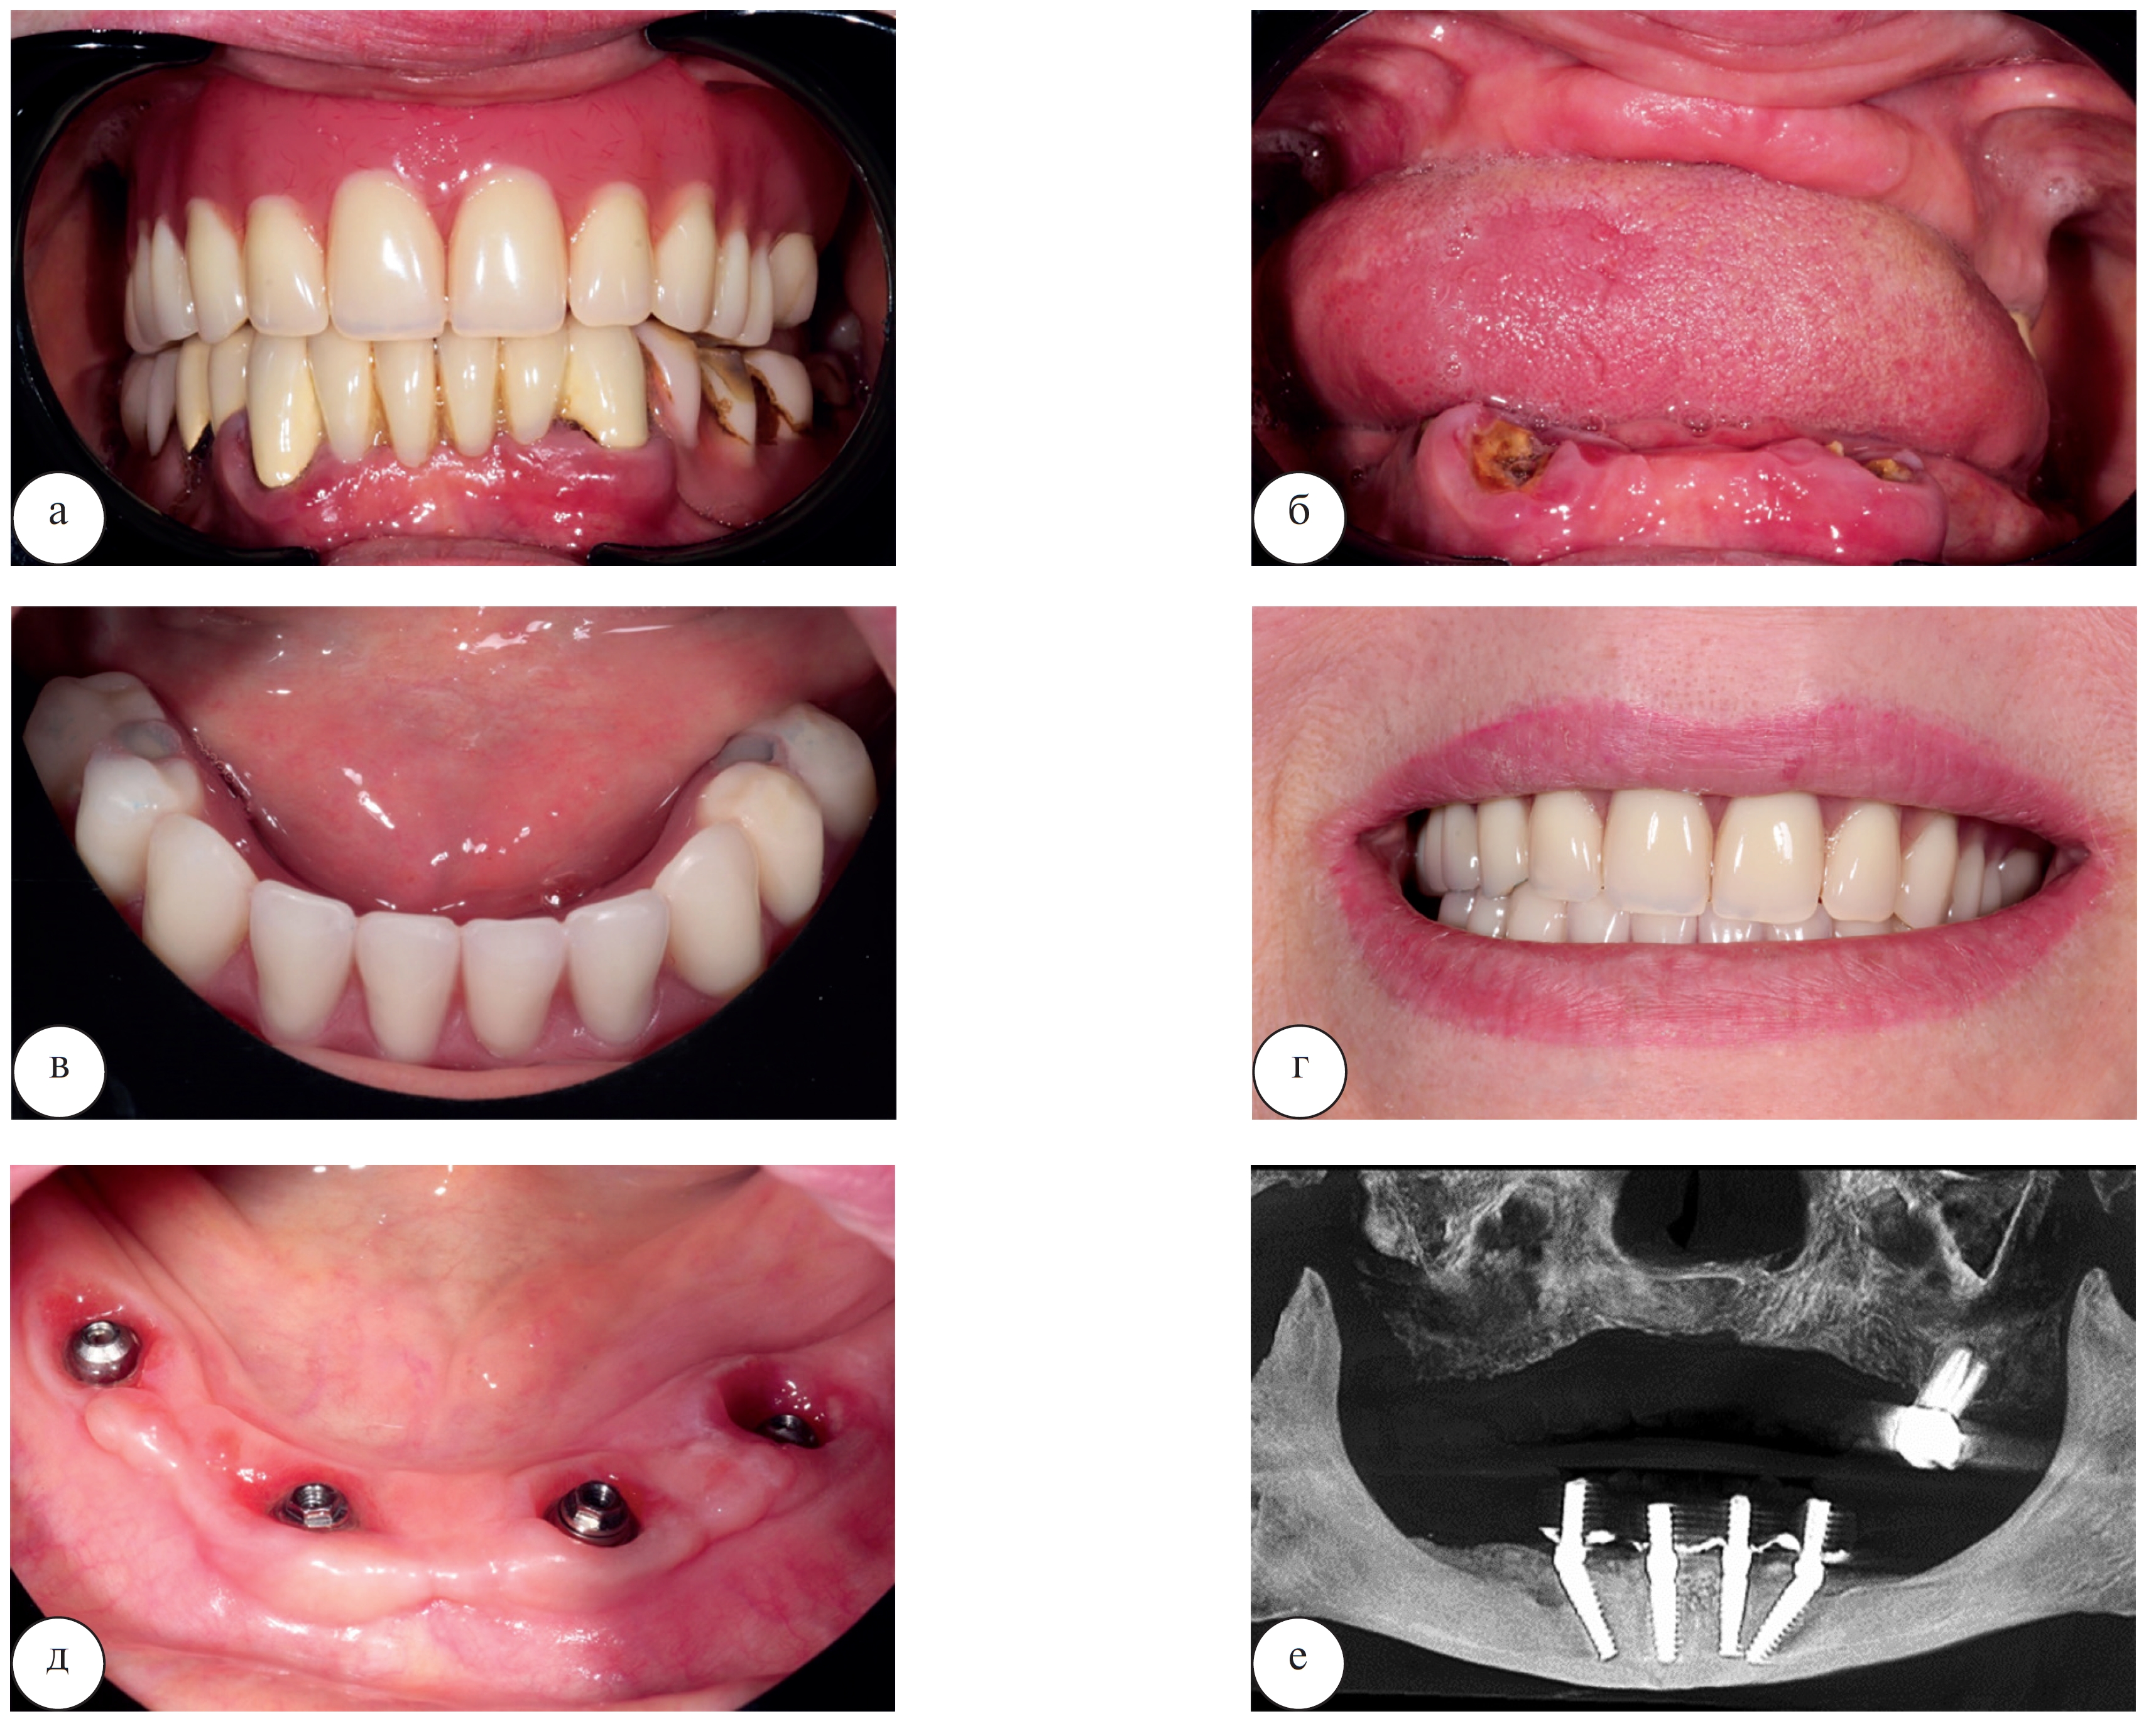

Для реализации этого протокола установка имплантатов осуществляется во фронтальном отделе челюстей, где атрофия костной ткани идет не такими быстрыми темпами. Два имплантата в области резцов устанавливаются параллельно, еще 2 – в боковых отделах челюсти (обычно в проекции премоляров) под углом для правильного распределения жевательной нагрузки. Клинический пример стоматологической реабилитации пациентки Ж. 49 лет с использованием четырех дентальных имплантатов представлен на рисунке 10.

Применение методики на 4 дентальных имплантатах позволяет также выполнить установку временной ортопедической конструкции сразу после проведения операции или в течение 3 дней после нее.

Рис. 10. Стоматологическая реабилитация с использованием протокола на 4 дентальных имплантатах у пациентки Ж. 49 лет: а – исходная клиническая картина в полости рта; б – клиническая картина в полости рта после удаления всех съемных конструкций; в – временный условно-съемный акриловый протез установлен по методике немедленной нагрузки; г – улыбка пациента с временными акриловыми протезами на верхней и нижней челюсти; д – вид слизистой в полости рта на контрольном осмотре через год после операции; е – срез компьютерной томограммы через год после операции